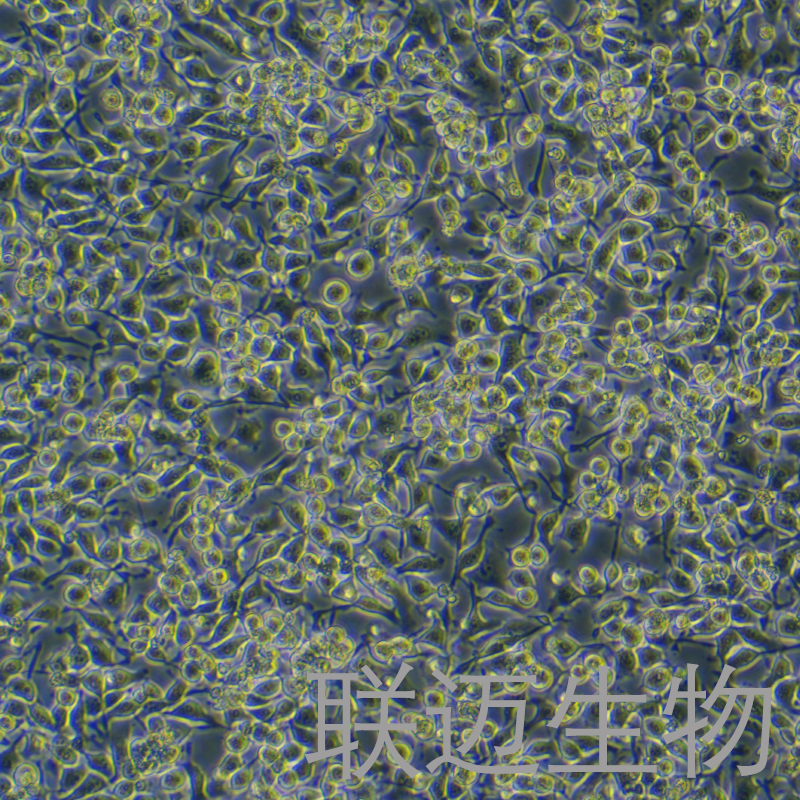

细胞系: 肿瘤细胞细胞形态: 上皮细胞样

生长状态: 贴壁细胞冻存条件: 无血清冻存液,液氮储存

细胞形态上皮细胞样

背景描述HO-8910细胞是于1994年从一位51岁的中国卵巢癌患者腹水中建立的;HO-8910细胞可裸鼠致瘤,其转移到裸鼠中形成的肿瘤集聚与患者原病灶处的形态一致。(STR检测位点同HELA)

生长培养基RPMI-1640+10% FBS+1% P/S